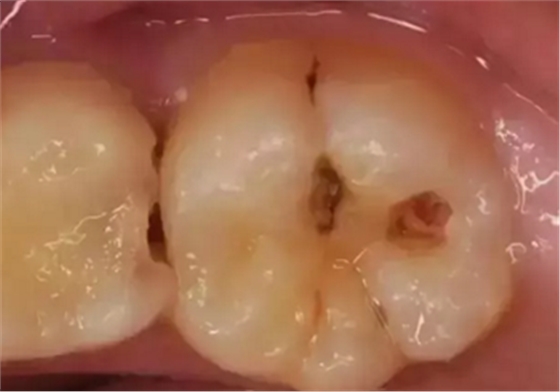

中齲——感染牙本質(zhì)表層:到這個階段,已經(jīng)能看到明顯的蛀洞,此時的病變位于牙本質(zhì)的淺層,牙齒會冷熱酸甜敏感,但是離開刺激物就沒有不適感。

深齲——滲透牙本質(zhì)深層接近牙髓:此時的病變已經(jīng)發(fā)展到牙本質(zhì)深層接近牙髓了,有明顯的蛀洞且較深,伴隨明顯的牙痛,遇到外界刺激痛感加重,牙齒變得很敏感,還會出現(xiàn)食物鑲嵌在牙洞的情況。